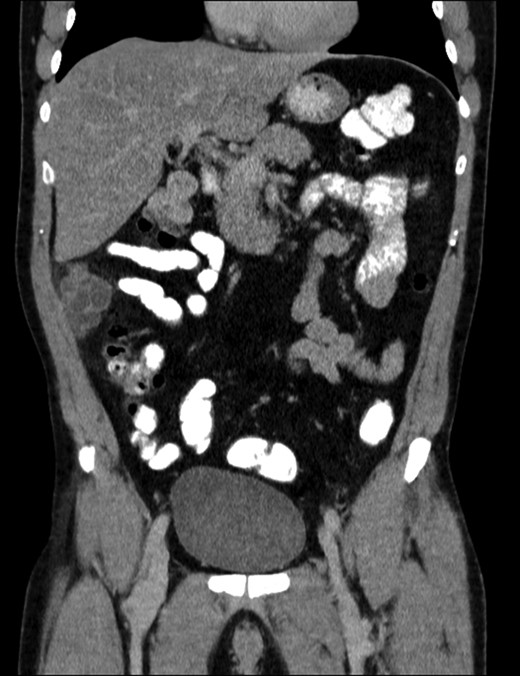

A 40-year-old Caucasian male, a past medical history of smoking, complaining from 5 years of occasional abdominal discomfort started having an acute, stinging pain in the right upper abdomen. A blood sample was taken that showed a smoldering increase of the transaminases and C-reactive protein of 22 mg/L. He was investigated in the outpatient setting with an abdominal ultrasonography that revealed a polycystic lesion of 9 cm of diameter in the right flank. He was than referred to our Hospital, where the physical examination was completely silent. A contrast enhanced CT scan of the abdomen revealed a polylobate hypodense formation, with multiple thin internal septa which are enriched after contrast (dimension 83 × 43 × 61 mm) (Figs 1 and 2). Radiologist posed differential diagnosis among peritoneal lymphangiomatosis, enteric duplication cyst and—even if less likely in a male without history of past abdominal surgery—benign multicystic peritoneal mesothelioma. After multidisciplinary discussion we proceeded to an exploratory laparoscopy that confirmed the presence of multiple cystic lesions of the peritoneum, some interesting the omentum, with a weak adherence with the ascending colon (Figs 3 and 4). We performed a complete excision of the neoformation, with free margin on omental fat. A small lesion of the colonic serosa was treated with a prophylactic continuous suture with Vycril 2-0. The postoperative course was uneventful ant the patient was discharged after 2 days without complications.

Computed tomography image results: (1) contrast enhanced sagittal reconstruction showing the right flank neoplasm.